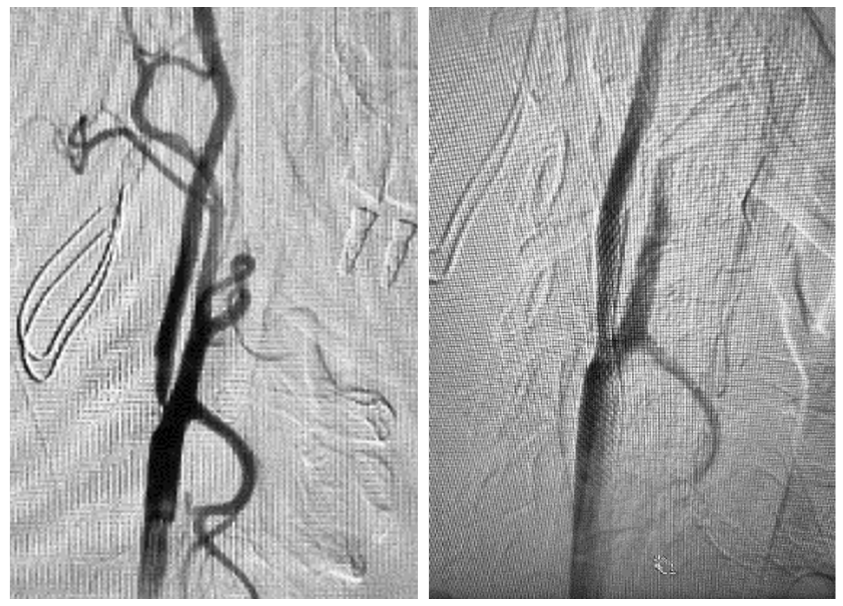

导引导管入路示意图(左)与借助望远镜技术将导引导管“U型”送入右侧颈内动脉病变远端(右)

术中,在成功穿刺右侧桡动脉后,张小峰带领神经内科主治医师王也、医师沈懿,借助“望远镜”技术(同轴技术),先后将长导丝、造影管和导引导管送入至病变远端,以弥补普通导引导管无法通过迂曲血管的不足,随后采用球囊预扩张技术,对病变部位的血管直径及病变狭窄等情况进行探查。在撤出过程中,张小峰凭借经验及时调整系统张力,以球囊作为锚定点将导管精准定位,避免了术中容易出现的导管脱出问题。介入团队继续使用“特洛伊木马”技术,谨慎输送并于狭窄处精准释放支架。复查造影,右侧颈内动脉起始部的重度狭窄完全开通。不到1小时,手术顺利结束。

术前脑血管造影示右侧颈内动脉起始部极重度狭窄(左)

与术后复查造影示右侧颈内动脉起始部狭窄完全开通(右)